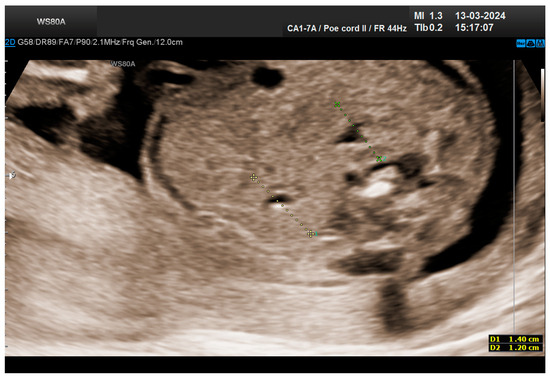

The combined test result indicated a low risk for trisomies, preeclampsia, and intrauterine growth restriction. However, during the ultrasound examination, the absence of the right renal tissue in the right parasagittal sections was noted (Figure 1). Examination of the embryo in axial sections demonstrated the presence of a relatively well-defined acoustically heterogeneous echogenic mass situated anterior to the spine, in sonographic contact with the renal tissue image correctly occupying the left lumbar fossa (Figure 2). Those aspects suggested the existence of a renal anomaly of crossed fused renal ectopia. No other embryonic anomalies were detected, the bladder image was present, and the amniotic fluid volume was normal. The calculated gestational age corresponded to the ultrasound estimate. The suspicion of crossed fused renal ectopia was maintained during a subsequent reevaluation at 17 weeks of pregnancy (Figure 3 and Figure 4).

Figure 1. Empty right renal fossa (circled in red)—first-trimester morphology scan at 13 weeks and 2 days.